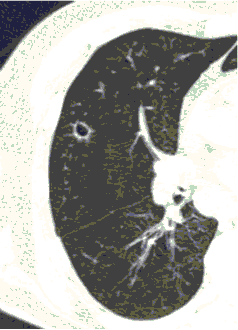

У больных с факторами риска COVID-ИА следует исключить при рефрактерной к адекватной антибактериальной терапии лихорадке 3 дней или нового эпизода лихорадки после нормализации t тела 2 дней, нарастании дыхательной недостаточности, а также появлении кровохарканья, боли в груди или шума трения плевры. При COVID-ИА на КТ или РГ легких выявляют двусторонние или односторонние очаги консолидации или деструкции. При наличии указанных клинических и радиологических признаков COVID-ИА показана бронхоскопия с получением БАЛ из пораженного сегмента, при интубации пациента возможно повторное получение трахеального аспирата (ТА) или небронхоскопического лаважа (НБЛ).

КТ имеет высокую чувствительность в выявлении изменений в легких, характерных для COVID-19. Применение КТ целесообразно для первичной оценки состояния ОГК у пациентов с тяжелыми прогрессирующими формами заболевания, а также для дифференциальной диагностики выявленных изменений и оценки динамики процесса. КТ позволяет выявить характерные изменения в легких у пациентов с COVID-19 еще до появления положительных лабораторных тестов на инфекцию с помощью МАНК. В то же время, КТ выявляет изменения легких у значительного числа пациентов с бессимптомной и легкой формами заболевания, которым не требуется госпитализация. Результаты КТ в этих случаях не влияют на тактику лечения и прогноз заболевания при наличии лабораторного подтверждения COVID-19. Поэтому массовое применение КТ для скрининга асимптомных и легких форм болезни не рекомендуется. При первичном обращении пациента с подозрением на COVID-19 рекомендуется назначать КТ только при наличии клинических и инструментальных признаков дыхательной недостаточности (SpO2 < 95%, ЧДД > 22).

4. Все выявляемые при лучевых исследованиях признаки, включая КТ-симптомы, не являются специфичными для какого-либо вида инфекции и не позволяют установить этиологический диагноз. Вне клинической (эпидемической) ситуации они не позволяют отнести выявленные изменения к пневмонии COVID-19 и дифференцировать их с другими пневмониями и невоспалительными заболеваниями. Данные лучевого исследования не заменяют результаты обследования на РНК SARS-CoV-2. Отсутствие изменений при КТ не исключает наличие COVID-19 и возможность развития пневмонии после проведения исследования.